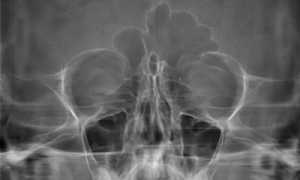

Врач ставит диагноз, основываясь на результатах опроса и осмотра. Специалист обязательно уточняет, болит ли лоб пациента. При осмотре он фиксирует состояние носовых ходов и пазух. Диагноз также требует рентгенографического подтверждения или же результатов томографии.

При пальпации было выяснено, что лоб при надавливании болит сильнее. По результатам осмотра и диагностической рентгенографии был поставлен диагноз: обострение хронического двустороннего гайморита.